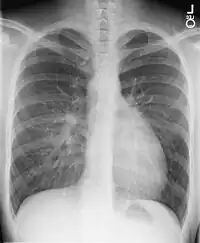

X-ray showing characteristic finding in case of Transposition of the great vessels which is called egg on side sign

Chest X-Ray: On chest X-ray (CXR), transposition of the great vessels typically shows a cardio-mediastinal silhouette appearing as an "egg on a string ", in which the enlarged heart represents an egg on its side and the narrowed, atrophic thymus of the superior mediastinum represents the string.[4]